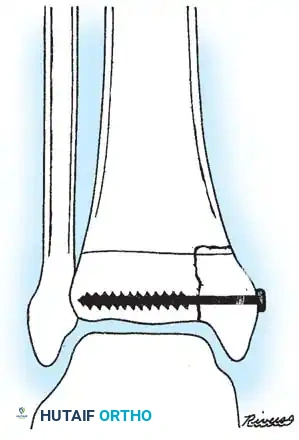

Fig. 33-175: Fixation of a tongue-type Salter-Harris III fracture utilizing cancellous screws.

5. Fixation:

* In older children and adolescents nearing skeletal maturity, utilize 4.0mm or 4.5mm partially threaded cancellous bone screws to achieve interfragmentary compression.

* In younger children with significant remaining growth potential, utilize smooth Kirschner wires (K-wires) placed transversely or horizontally to minimize the risk of physeal arrest.

Placement of transverse fixation pins.

Final construct utilizing cancellous screws for rigid fixation.